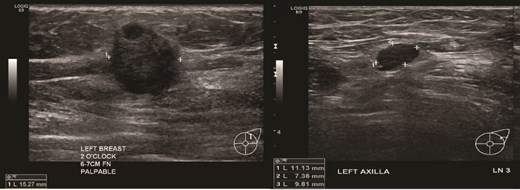

(Left) Ultrasound images of the left breast ill-defined hypoechoic mass; (Middle, Right) Ultrasound images of the axillary lymph nodes with cortical thickening and effacement of the fatty hilum.

(Left) Ultrasound image of the left breast hypoechoic lesion; (Right) Ultrasound image of one of several enlarged lymph nodes with effacement of fatty hilum.